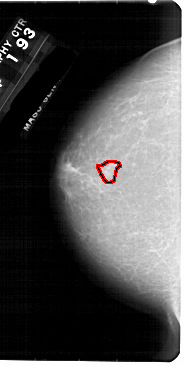

FILE: A_1948_1.LEFT_MLO.OVERLAY

TOTAL_ABNORMALITIES 1

ABNORMALITY 1

LESION_TYPE MASS SHAPE IRREGULAR MARGINS ILL_DEFINED

ASSESSMENT 4

SUBTLETY 3

PATHOLOGY BENIGN

TOTAL_OUTLINES 1

BOUNDARY